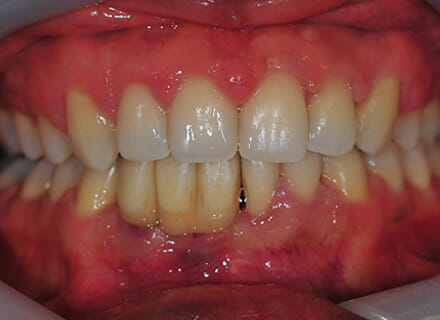

This patient came to us with 2 big issues: he had a number of failing teeth in the lower jaw at the front. Due to gum (periodontal) disease these teeth had come loose and started to grow apart splaying out in all directions. In the upper jaw the teeth had also started moving so that big gaps had appeared between them. We treated the gum disease to save most of the teeth and placed 2 implants in the lower jaw, placing 4 new teeth on top of them immediately (immediate dental implant treatment).

He then went to see Charlene who does our braces (orthodontics) and she placed some tooth coloured brackets. The braces pulled all the teeth together and levelled them off. Finally we fitted new ceramic implant bridge teeth to replace the lower temporary teeth we fitted initially.